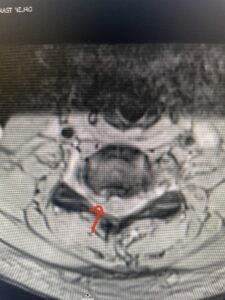

Fig 2a Sagittal and axial T2 weighted cervical MRIs demonstrating large C4 5 herniated disc with spinal cord compression red arrows

This 47-year-old male who four months prior was lifting weights developed sharp pain in his neck. After that he developed progressive numbness in his arms, neck pain and headache. He said that the right arm was worse than the left. On examination the patient had long tract weakness on the right side which included his triceps, finger extensors, hip flexors, and dorsiflexors. The patient did not have hyperreflexia. MRI (Fig. 2) demonstrated a massive, extruded disc herniation with severe cord compression. The patient because of progressive myelopathy and spinal cord compression was indicated for anterior cervical discectomy and fusion at C4-5 (Fig. 3). Patient had significant improvement of weakness and numbness post operatively.

Fig. 2a Sagittal T2-weighted cervical MRI demonstrating large C4-5 herniated disc with spinal cord compression (red arrow)

Fig: 2b Axial T2-weighted cervical MRI demonstrating spinal cord compression from C4-5 herniated disc (red arrow)